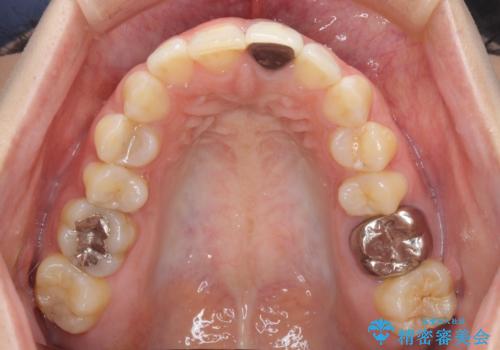

- 前歯をメタルの被せものにしており、セラミックに変えるのを希望された患者様です。

土台も金属だったため、歯がかなり黒く変色していました。

今回は歯自体が黒くなって歯茎から透けて見えている黒ずみのため、セラミック治療で改善させることは困難だというお話をしました。その上でできる範囲できれいに治療することになりました。

今回のように歯自体が金属イオンで黒く変色すると、被せものをメタルフリーにしても黒ずみをすべて隠すのは困難になります。一方、被せものの金属が見えていることが原因の黒ずみの場合は、セラミック治療できれいになりますので、気になる方は一度ご来院ください。